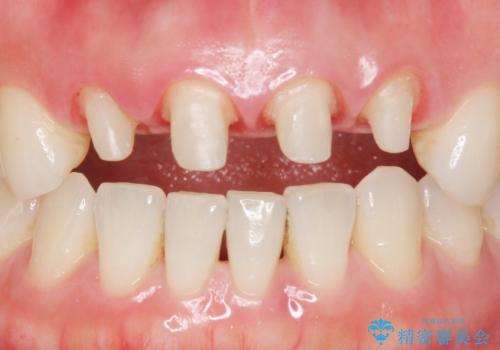

- 10年前に美容外科クリニックで前歯を治療したところ、あまりに不自然で逆にコンプレックスになってしまったことを主訴に来院された患者様です。

前歯4本の被せものは連結されており、不自然なだけではなく清掃性も悪く歯茎が著しく腫脹していました。

レントゲンを撮影したところ土台の植立も不十分であったため、土台からやりかえることにしました。

歯茎の腫脹が顕著であったため、適合の良いオーダーメイドの仮歯に変え、歯茎の状態が良くなるまで1ヶ月待ったのち型取りを行いました。